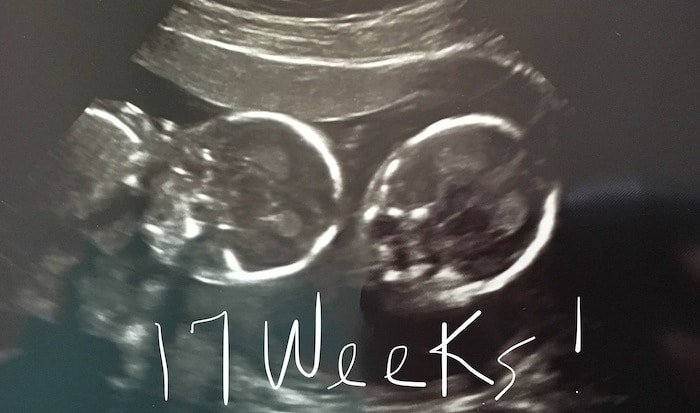

- Ultrasound Photos at 17 Weeks Pregnant With Twins

Ultrasound Photos at 17 Weeks Pregnant With Twins